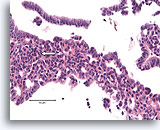

Lobulair carcinoom, Borst FNA, celblok.

Lobulaire carcinoomcellen lijken in het stromaweefsel te zijn ingebed, zodat de indruk wordt gewekt van hypercellulariteit. Dit kan de reden zijn waarom cytologische preparaten van een lobulair carcinoom vaak weinig maligne cellen tonen.

20X

Lobulair carcinoom, Borst FNA, celblok.

Lobulaire carcinoomcellen lijken in het stromaweefsel te zijn ingebed, zodat de indruk wordt gewekt van hypercellulariteit. Dit kan de reden zijn waarom cytologische preparaten van een lobulair carcinoom vaak weinig maligne cellen tonen.

20X